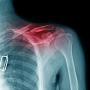

• Lūzums